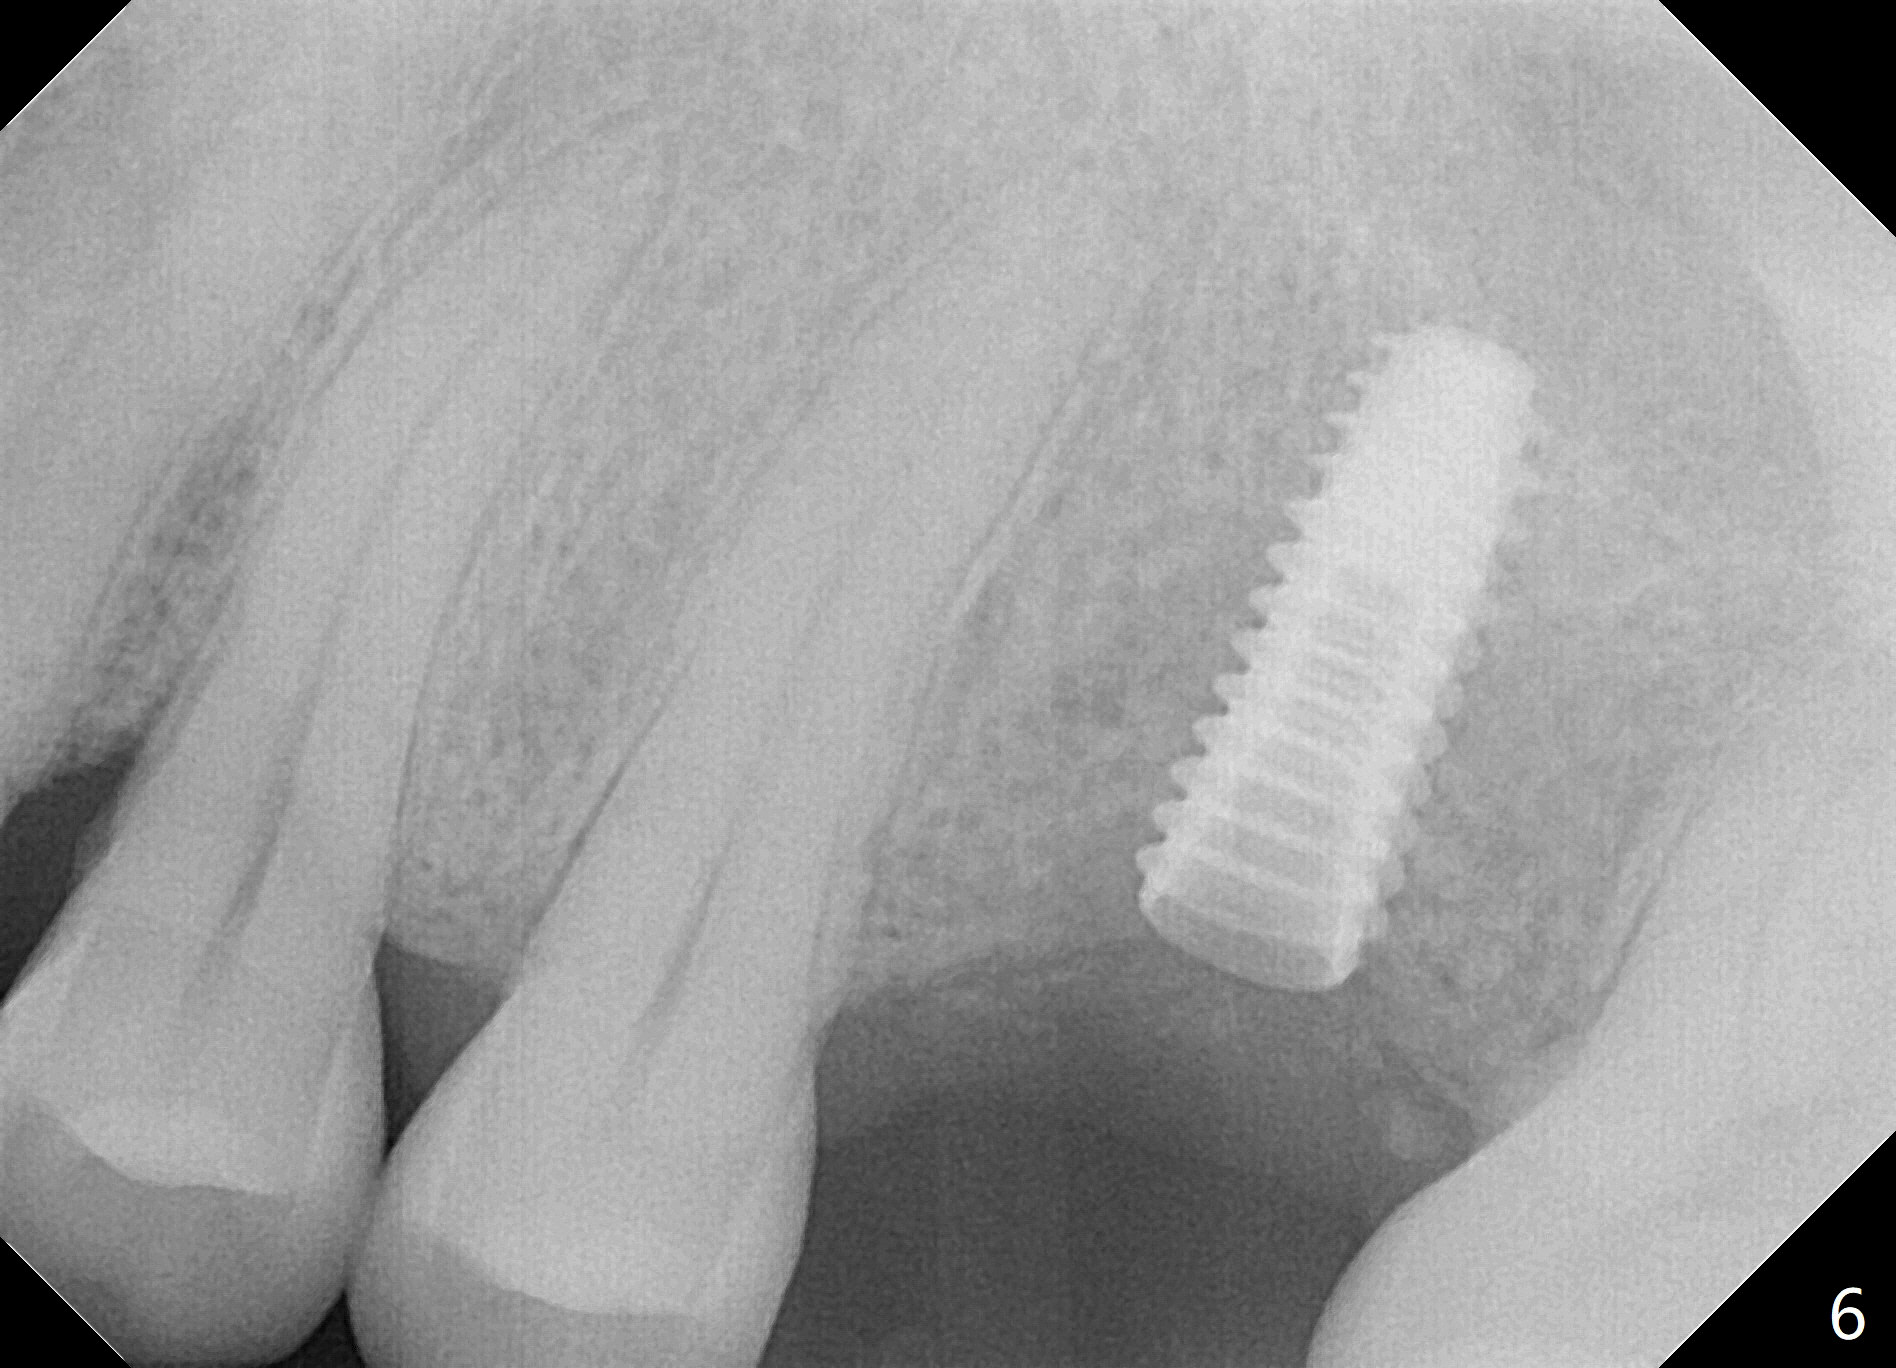

The edentulous area at #14 is moderately atrophic, After incision, the bone is too hard for #15 blade for bone expansion. Osteotomy is initiated with 1.2 mm drill, followed by insertion 1.3/2.3 mm bone expander (Fig.1). Use the same instruments are reused twice to change the trajectory (Fig.2,3). Finally Lindamann bur is utilized to move the osteotomy distally by ~ 2 mm; bone expansion continues until 2.4/3.7 mm expander for 13 mm with 50 Ncm (Fig.4). The last expander 3/4.4 mm barely enters the osteotomy for 6 mm. A 3.7 mm drill has to be used for 12 mm before placement of a 4.5x11.5 mm implant with >35 Ncm (Fig.5). A 5.5x5(3) mm abutment is placed with allograft (<) placed around the implant. Following suturing, periodontal dressing is applied around the implant. The abutment dislodges 3 months postop (Fig.6). Crown is delivered 3 weeks later. The abutment screw is retightened ~ 2 months later. He is a bruxer. The abutment screw is loose again <2 years post cementation (6 months post #18 screw retightenting and occlusal reduction), probably related to distal implant placement (Fig.7).